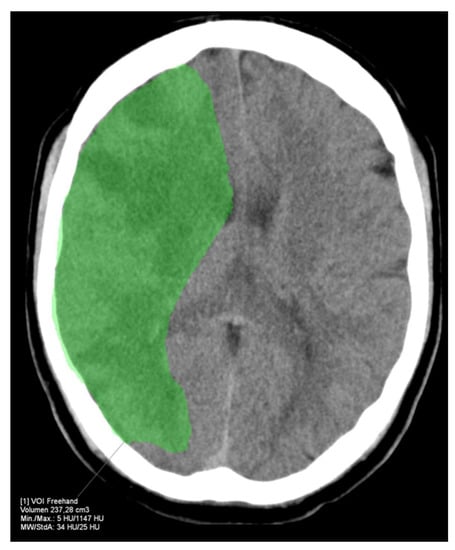

2.1.2. Imaging Analysis